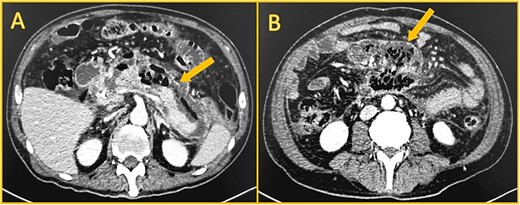

Local complications were suspected, and a contrast-enhanced abdominal computed tomography (CT) was done. It revealed a peripancreatic and perihepatic fluid. The pancreas was enlarged and had several areas of necrosis with gas bubbles (Fig. 1).

Contrast-enhanced computed tomography. A: Perihepatic fluid. B: The pancreatic head, body, and tail have non-enhancing areas compatible with necrosis. C: Dilated biliary duct (leftmost arrow) and Wirsung (rightmost arrow). D: Peripancreatic fluid.